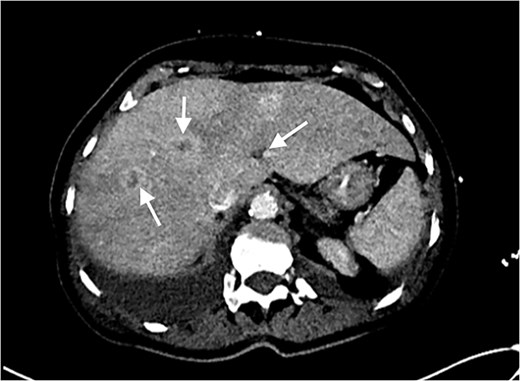

Echocardiography revealed a 1.2 cm pedunculated mass attached to the anterior mitral valve leaflet (AMVL) with severe mitral regurgitation (Fig. 1). Computed tomography imaging revealed multiple hepatic lesions (suspected septic emboli, Fig. 2), and a cavitating mass in the posterior aspect of the left upper lobe of the lung (Figs 3 and 4). Magnetic resonance imaging showed multiple cerebral lesions (Fig. 5), also thought to be septic emboli. Her presentation was suspected to be due to infective endocarditis rather than ischaemic, as troponin was negative, and coronary angiography was unremarkable. She was therefore treated promptly with intravenous vancomycin and gentamicin as per local antimicrobial guidelines. However, she failed to recover, and her case was reviewed in the regional in-house urgent cardiac surgical multidisciplinary team meeting. Considering her persistent fever, as well as the recurrent emboli, the decision was made to transfer her to our centre for emergency surgery.

Axial CT image of the liver, showing multiple lesions, initially thought to be septic emboli.